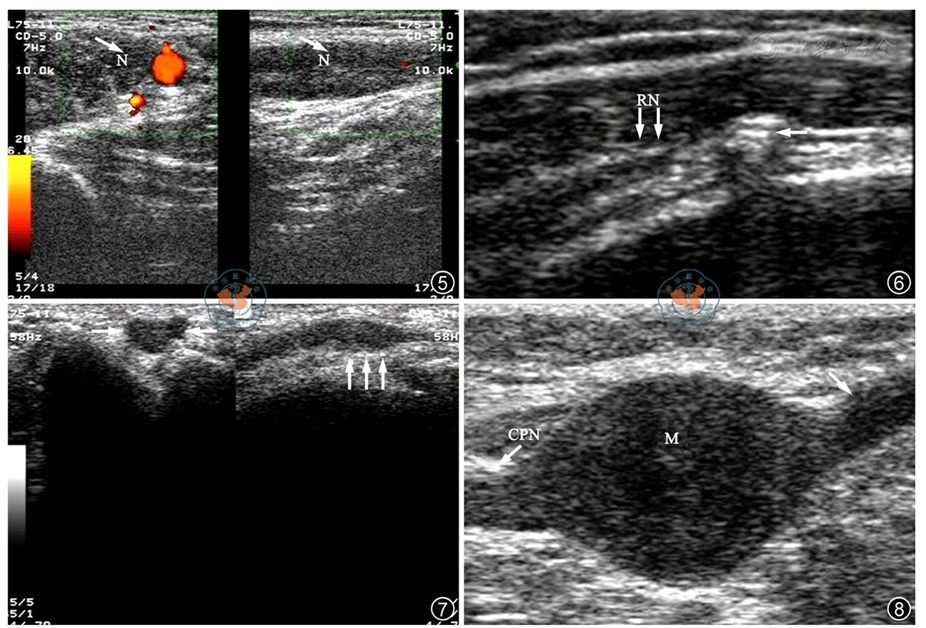

图3,4 臂丛神经损伤超声声像图。超声提示:左侧臂丛神经发出根部未见明显异常,中下干及腋下正中神经明显增粗水肿周围瘢痕形成,可疑节后损伤

图8 腓总神经肿瘤超声声像图